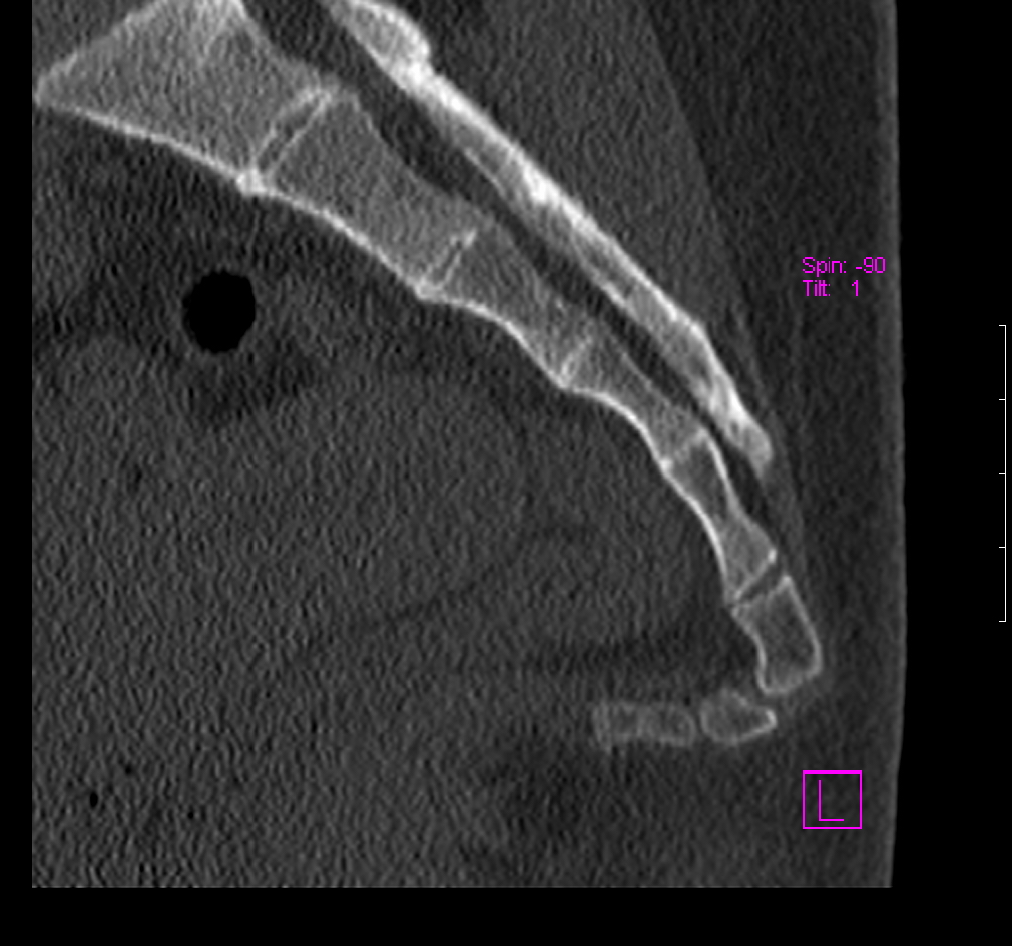

Рентгеновские снимки крестцово-копчикового отдела позвоночника